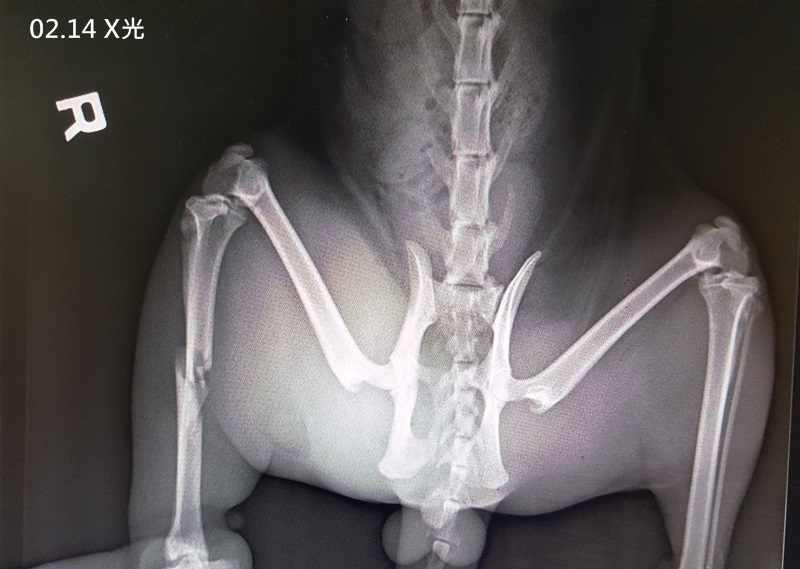

到了醫院的馬辣緊張到屎尿齊發,醫師進行檢查,他的右後腿骨折、並可能是蜂窩性組織炎使得整隻腿腫脹、尚未結紮,醫師於隔日將馬辣麻醉後進一步檢查,全套血檢白血球偏高、二合一檢查為陰性、x光檢查確定右後肢骨折,醫師先以抗生素治療感染,因骨折情況較為繁複,故轉院做進一步處理。

2月14日 進行全套血檢、二合一檢驗、X光、打長效抗生素、除蚤。